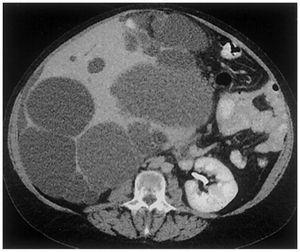

La enfermedad poliquística hepática (EPQH) es la manifestación extrarrenal más frecuente y se asocia con ambos genotipos: PKD1 y PKD2. La EPQH también puede presentarse como una enfermedad genética distinta, en ausencia de quistes renales (figura 7). Al igual que la PQRAD, la EPQH es genéticamente heterogénea, con dos genes identificados (PRKCSH en el cromosoma 19 y Sec63 en el cromosoma 6).

Figura 7. Tomografía computada que muestra numerosos quistes hepáticos en un paciente con poliquistosis hepática autosómica dominante (PQHAD) sin afectación renal.